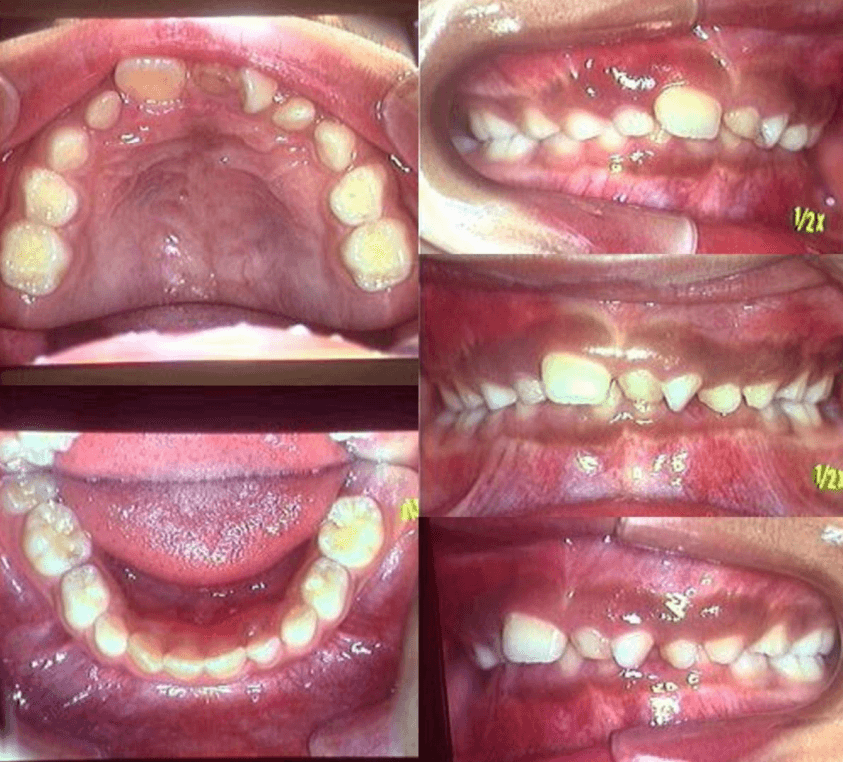

早期矯正治療 反対咬合症例②

主訴 | 前歯の噛み合わせが逆で、見た目や食事に違和感があることを心配されて来院されました。 |

---|---|

診断結果 | 7歳8か月の男児 前歯の反対咬合診断 |

治療内容 |

|

治療後の経過 | 早期矯正治療は11歳5か月で終了し、現在は3〜4か月ごとの定期検診で経過観察中で、今後本格的な矯正治療へ移行予定です。 |

治療期間 | 3年6か月 |

治療費用 | 430,000円(税別) |